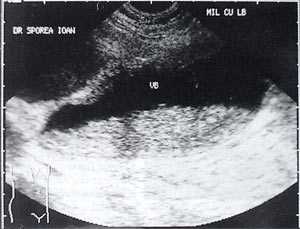

Кроме типичного вида, "желчный сладж" может иметь особый вид, похожий на круглое полипоидное объемное образование с острыми краями или неравномерным контуром ("опухолеподобный желчный сладж" или "сладжевые шарики" [12, 13]). При изменении положения больного видны перекатывающиеся или разрушающиеся шарики сладжа, затем снова формирующие исходное объемное образование (рис. 2-8).

Рис. 4. "Желчный сладж" у больного с циррозом печени.

Рис. 5. Желчный пузырь, заполненный сладжем, у больного циррозом.

Рис. 6. Желчный пузырь и "желчный сладж".

Рис. 7. "Желчный сладж" в виде шара.

Рис. 8. Шароподобный "желчный сладж".